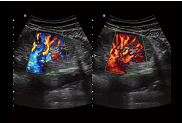

VS Flow

es una función en base al flujo Doppler de alta resolución espacial. Para identificar el cambio vectorial de las señales de Doppler del flujo sanguíneo. Se recoge un 30% más de señales laterales para mejorar la sensibilidad de todo el flujo, especialmente el flujo de velocidad lenta en los dedos y al riñón.

VS Flow mejora significativamente la sensibilidad y la resolución del flujo sanguíneo, lo que ayuda a los médicos a maximizar el valor de la aplicación clínica.